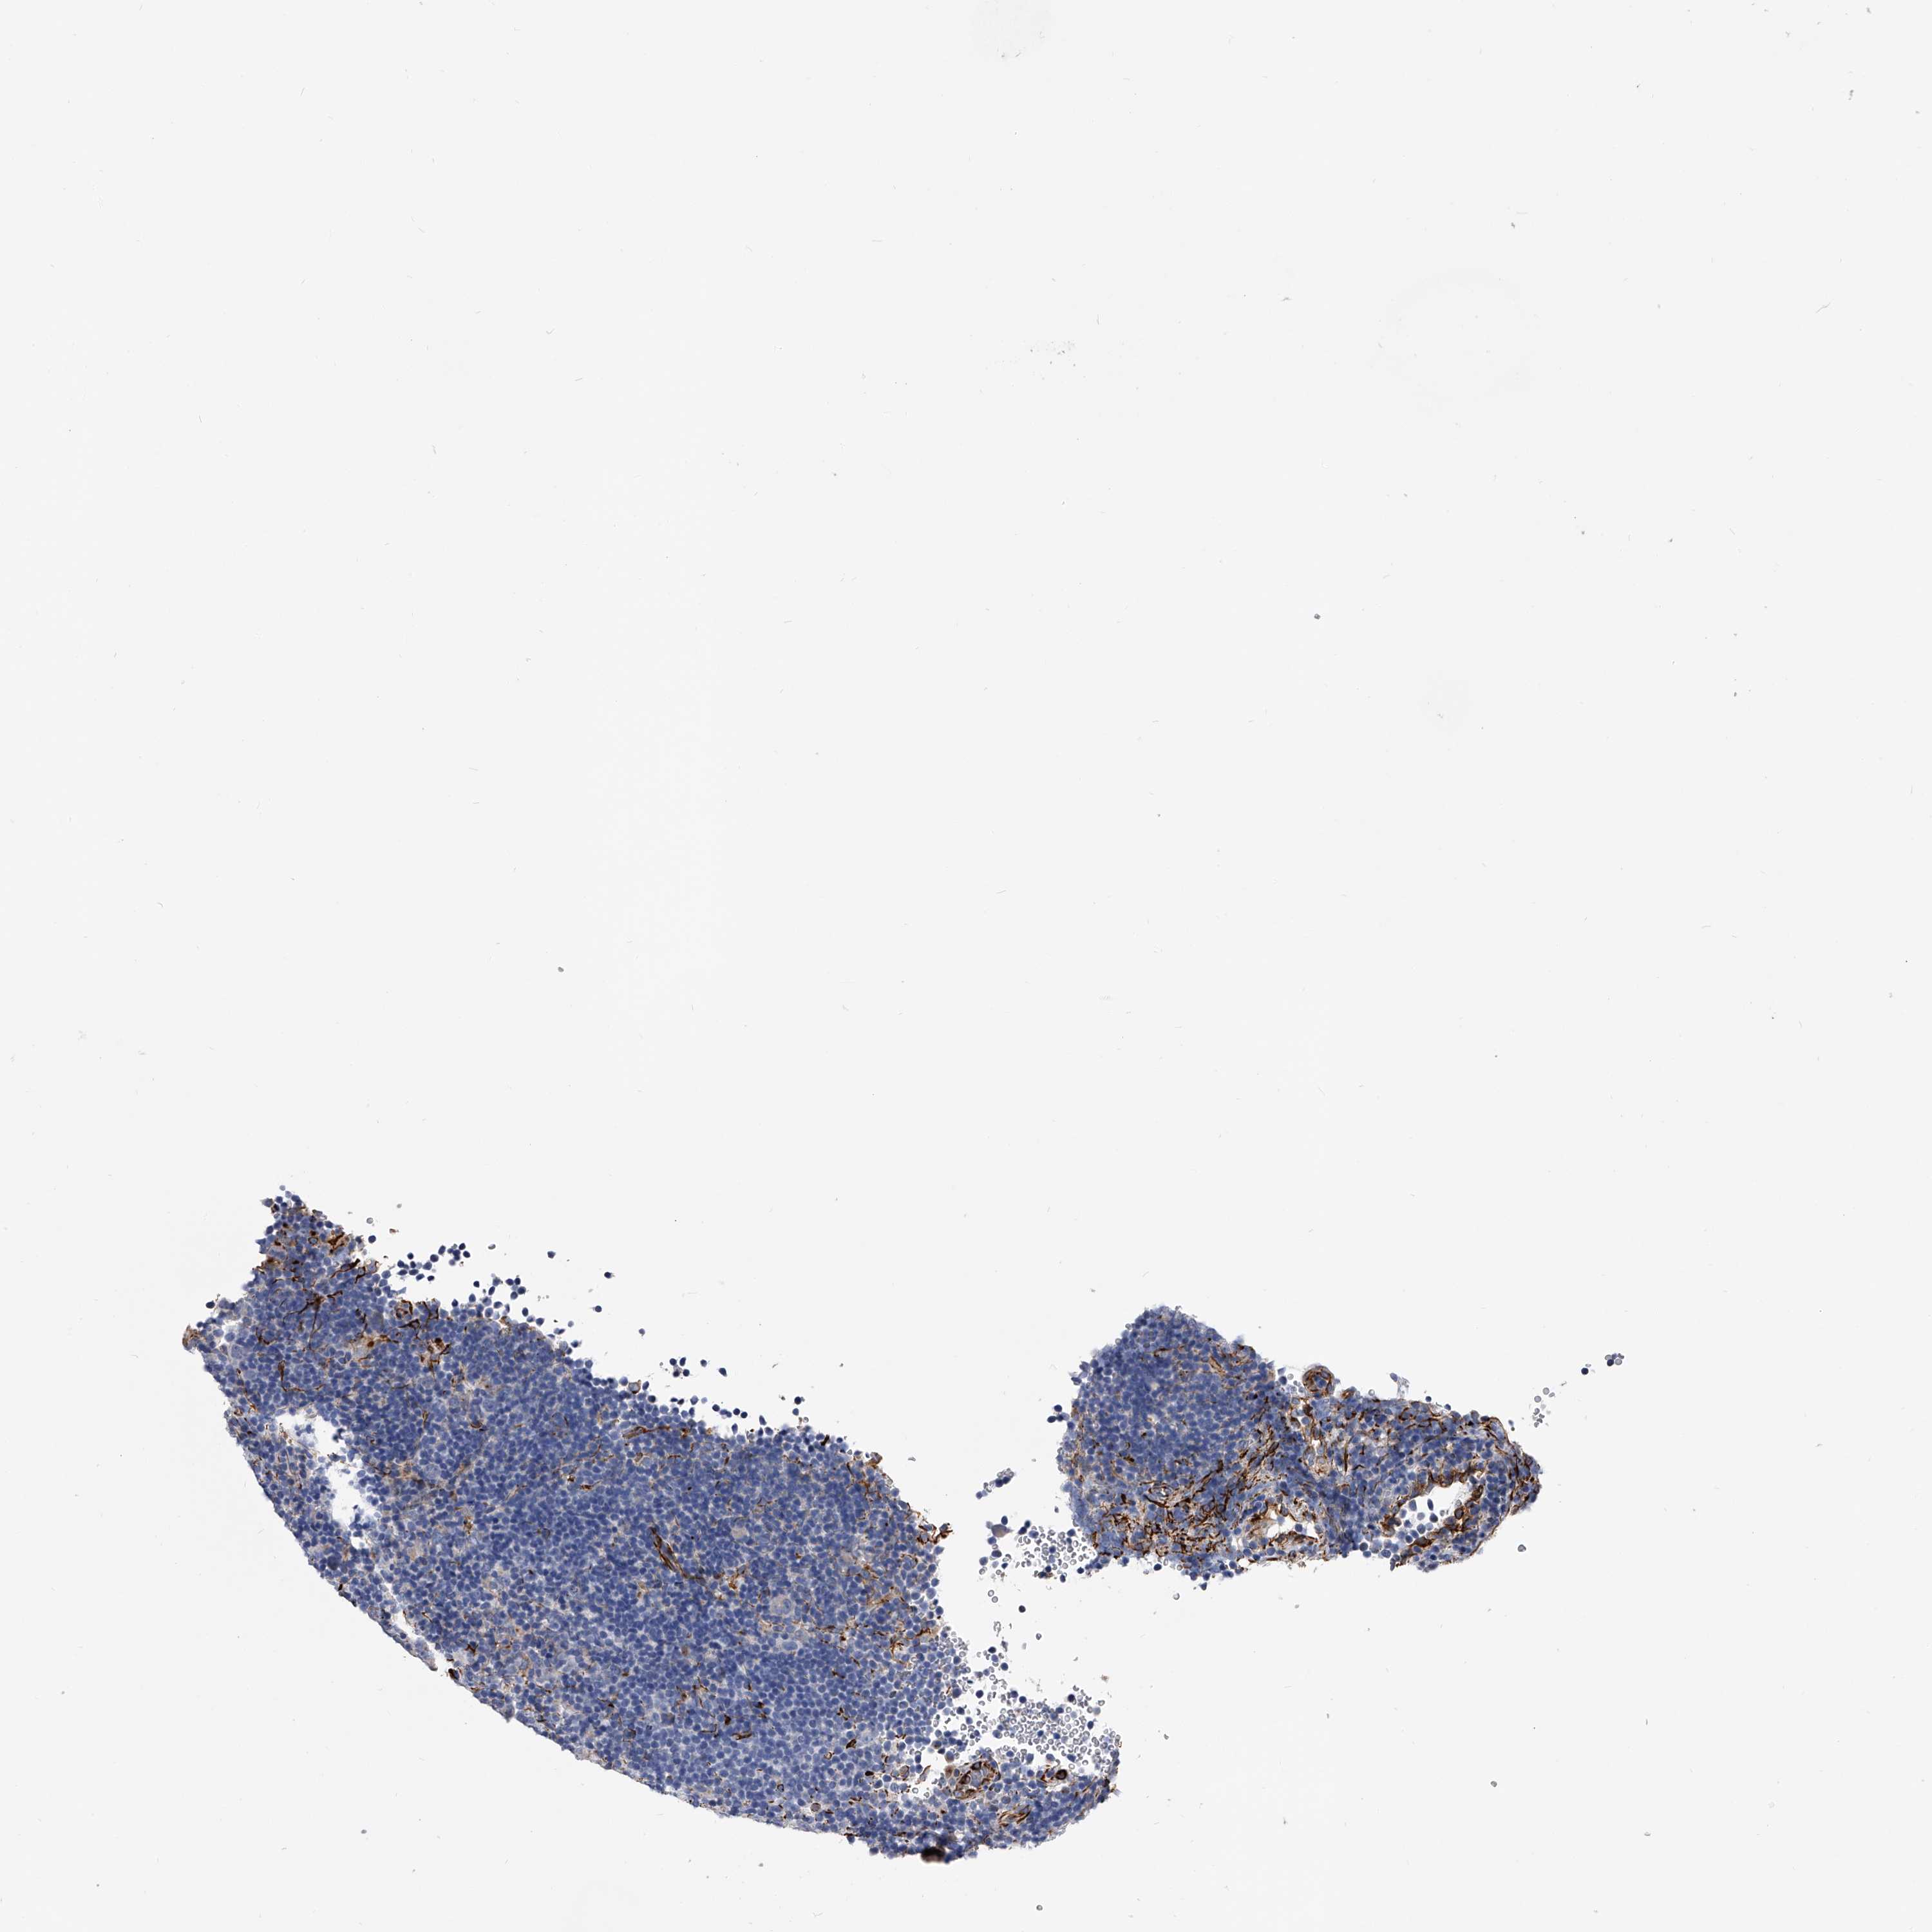

LYMPHOMA